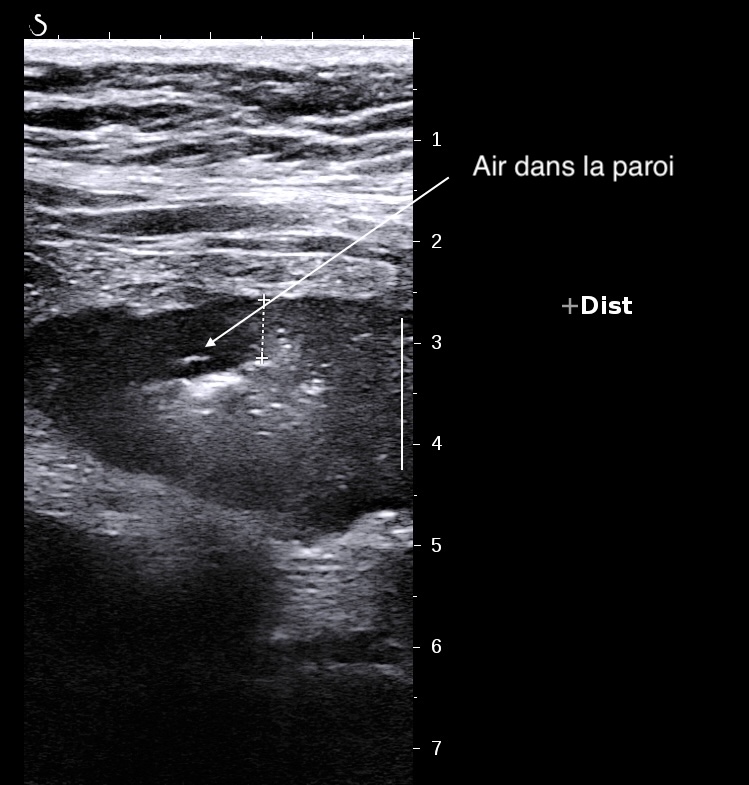

Paroi hypoéchogène, irrégulière en périphérie, présence d'air dans la paroi due aux ulcères

On peut voir des irrégularités de surface, la présence d'air dans la paroi et l'extension de l'inflammation qui atteint la graisse péricolique, il y a alors risque de perforation ).

Paroi totalement déformée, avec ulcères en surface, bord externe irrégulier, graisse infiltrée, voire épanchement liquidien

Disparition de la structure en couches